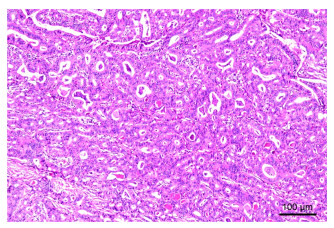

本文报道1例罕见的老年胸椎多发骨嗜酸性肉芽肿(eosinophilic granuloma, EG)病例。患者男性,66岁,因“腰背疼痛伴乏力两年余,加重三个月”就诊。经糖皮质激素联合免疫抑制保守治疗后临床表现及实验室检查好转,病理活检显示肉芽肿组织消失,后因病变部位出现压缩性骨折行外科手术治疗。该病例提示糖皮质激素联合环磷酰胺治疗成人多部位骨嗜酸性肉芽肿患者是可行的。